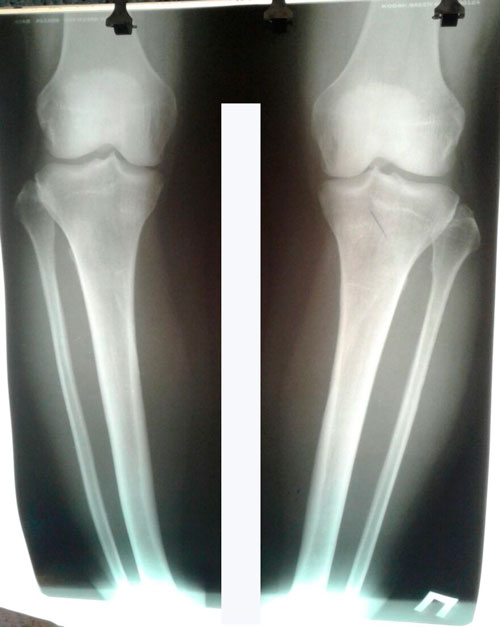

Исходник - 44 года.

Дата операции 21.03.2017г.

РЕНТГЕН ДО ОПЕРАЦИИ